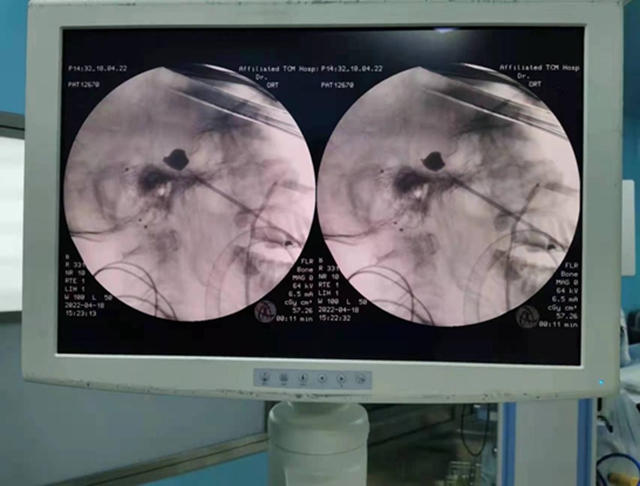

三叉神经微球囊压迫术怎么做?

三叉神经微球囊压迫术是一种从意大利引进的先进微创技术。整个手术过程在C臂影像引导下精准进行,术中将微球囊置入颅底的卵圆孔内,压迫三叉神经半月结3-5分钟后即取出球囊。